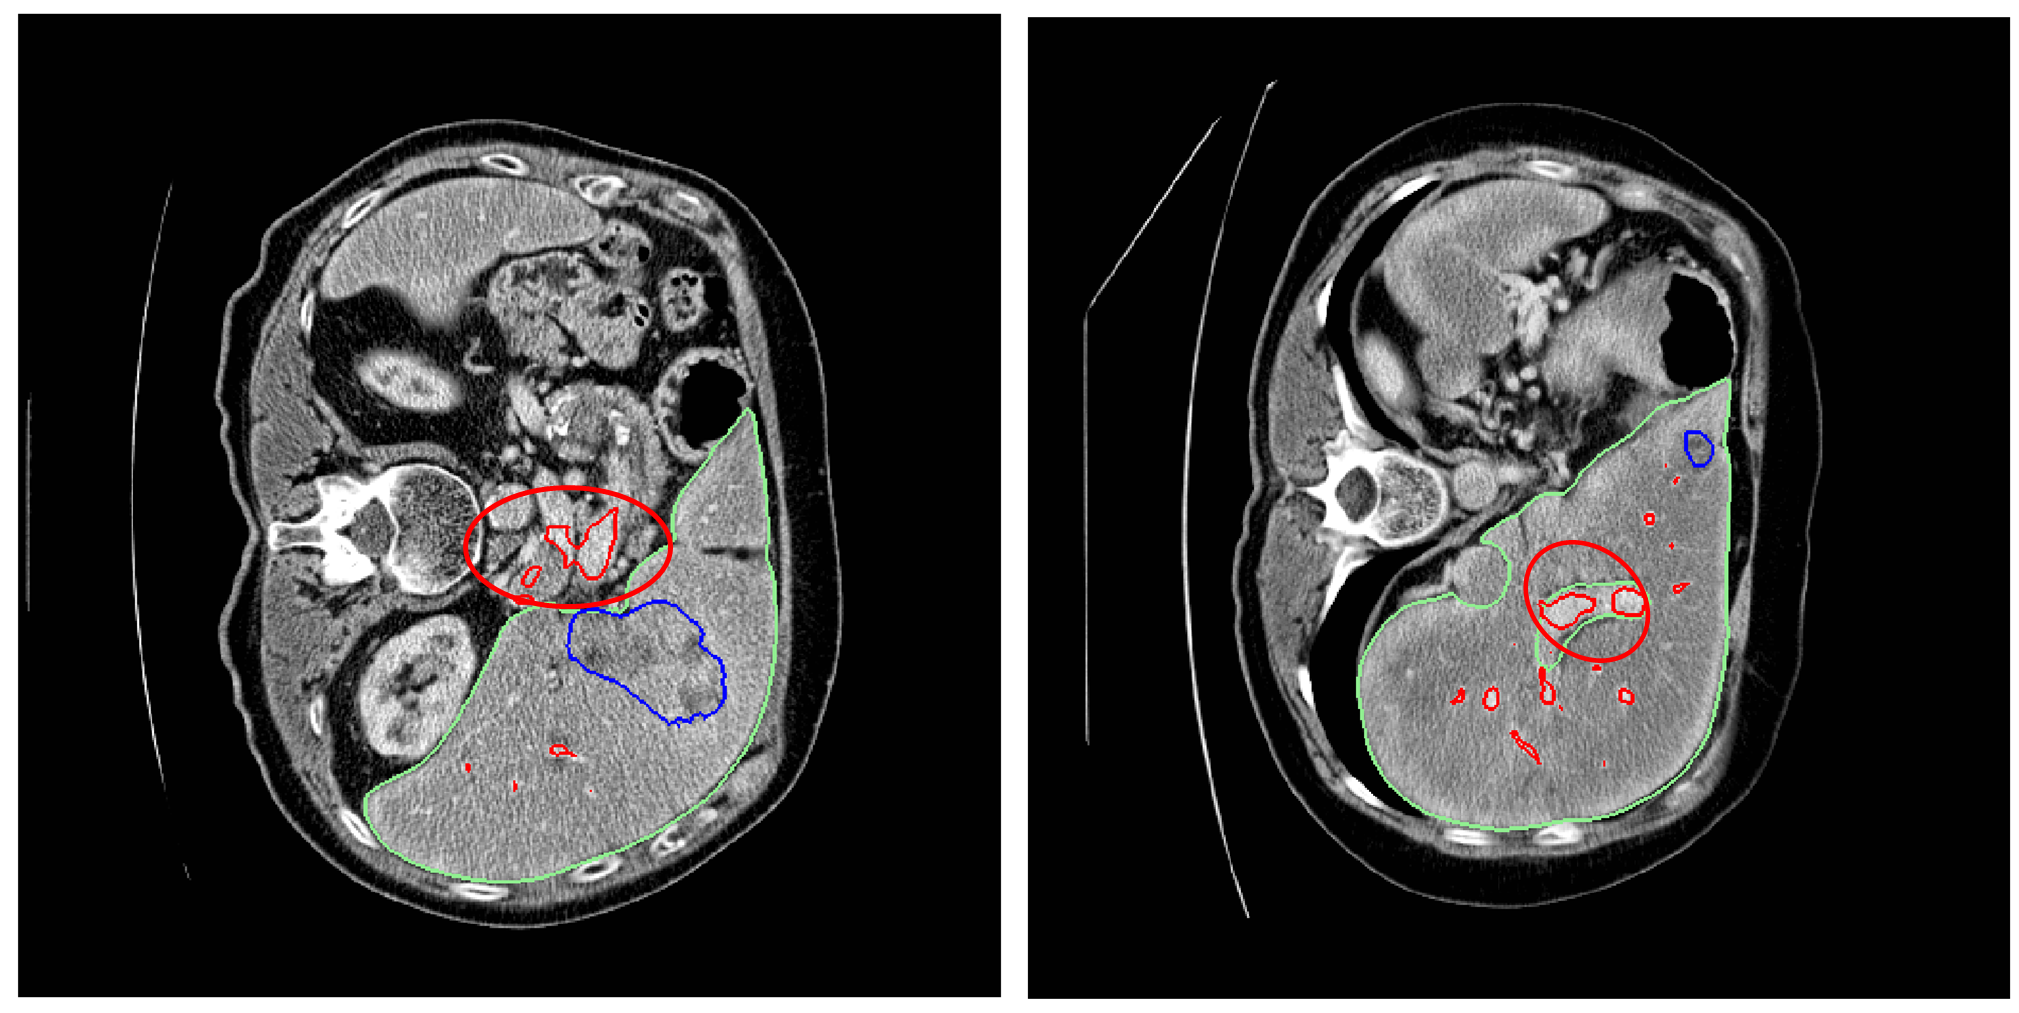

The application of the liver mask markedly enhanced the segmentation performance for tumors but did not yield similar improvements for vessels; in fact, vessel segmentation performance marginally declined. This disparity can be explained by two main factors: Firstly, the liver’s vessel structure possesses distinctive characteristics that make the liver mask less beneficial for vessel segmentation compared to tumor segmentation. Tumors, which can be mistaken for other organ tissues such as the kidneys, benefit from the application of the liver mask as it helps to exclude these non-tumor tissues. Secondly, the construction of liver masks sometimes excludes vessels. Consequently, when the liver mask is applied, it may inadvertently eliminate vessel voxels. Figure 11 illustrates this issue with two examples where vascular tissues are omitted following the application of the liver mask. In these examples, green represents the ground-truth liver mask, blue the ground-truth tumors mask, and red the ground-truth vessels mask.

Considering the advantages and challenges of applying liver delineation to subsequent ConvNets, liver masks are consistently used for both tumor and vessel tissues, with plans to modify the approach for vessel tissues in future studies. The learning rates (LRs) employed for tumor and vessel segmentation tasks are detailed in Tables 5 and 6, respectively. These tables provide the mean and standard deviation from five runs of 5-fold cross-validation.